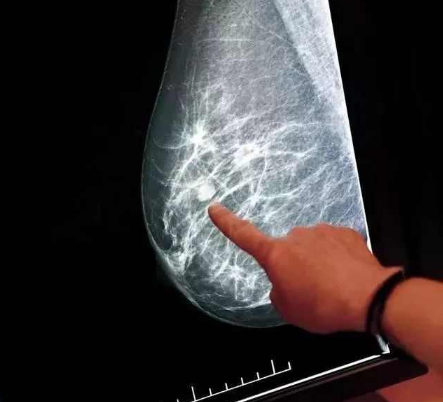

甲状腺肿瘤高发,这4个“行为”是高危因素,不可忽视!

在健康体检中被查出有甲状腺结节,如今早已不再是一件“天塌了”的事,近年来随着体检仪器精密度提高以及人们对甲状腺疾病的重视,在中国人群中甲状腺结节的检出率已经高达20%—60% ,高检出率的背后“肿瘤”阴影却一直如影随形。 “这60%的人群中,...[详细]